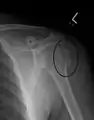

Fracture of the greater tuberosity of the humerus

Multi-fragmented, or comminuted fracture of the proximal humerus with involvement of the greater tuberosity

Proximal humerus fracture